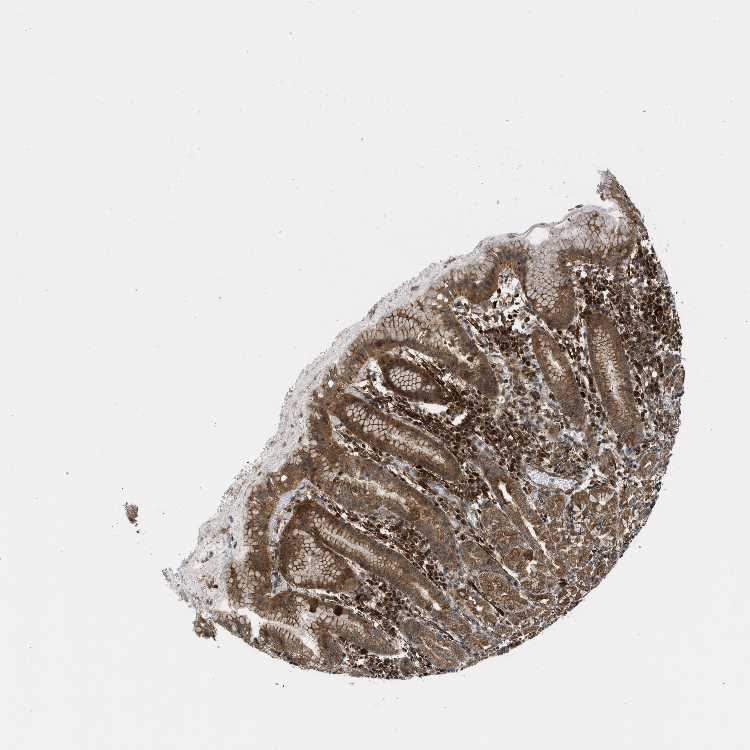

STOMACH 2 - Antibody stainingi

Antibody staining in the annotated cell types in the current human tissue is reported as not detected, low, medium, or high, based on conventional immunohistochemistry profiling in selected tissues. This score is based on the combination of the staining intensity and fraction of stained cells.

Each image is clickable and will lead to virtual microscopy that enables deeper exploration of all samples and also displays staining intensity scores, fraction scores and subcellular localization as well as patient and tissue information for each sample.

Antibody HPA018191

Glandular cells Medium